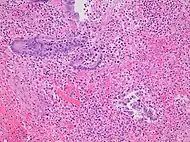

Pathology diagnosis of appendicitis can be made by detecting a neutrophilic infiltrate of the muscularis propria.

Micrograph of appendicitis and periappendicitis. H&E stain Micrograph of appendicitis showing neutrophils in the muscularis propria. H&E stain

Micrograph of appendicitis showing neutrophils in the muscularis propria. H&E stain Acute suppurative appendicitis with perforation (at right). H&E stain